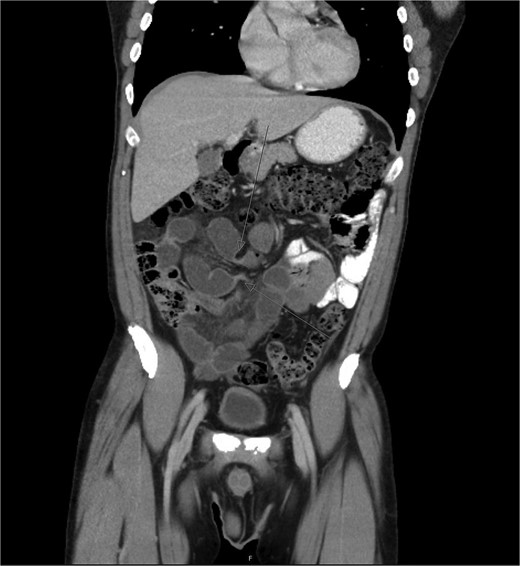

During diagnostic laparoscopy, a loop of jejunum was found to be transomentally herniated, congested but viable (Figs 2 and 3). Adhesiolysis was performed, and no small bowel resection was required. The patient was discharged on postoperative day 2 after an uneventful recovery and has not experienced any complications since.

Intraoperative image showing the omental defect after reduction of the herniated loop of jejunum.